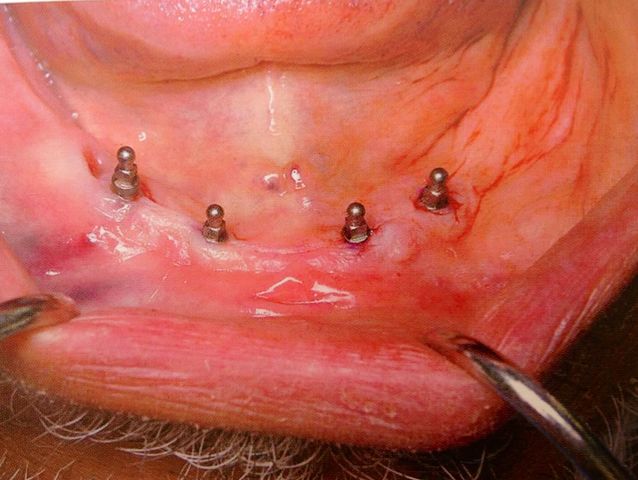

Colocación de 4 mini implantes